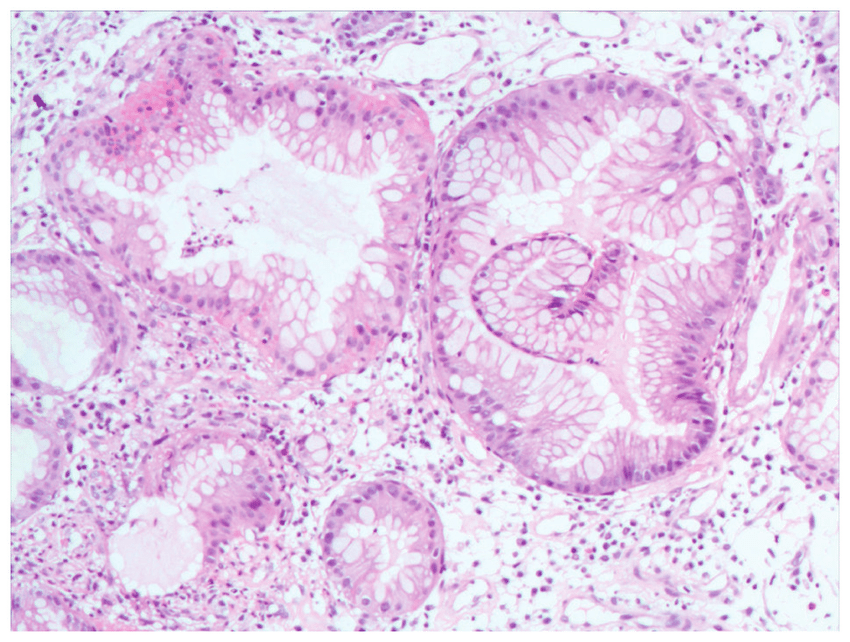

There were no fibroblasts detected in the primary cultures and the cells showed the expected morphology of cobblestone appearance and domes. The cells also expressed the epithelial cell marker cytokeratin and the proximal tubular marker called aminopeptidase A. RCC primary cultures too displayed a mixed morphology that is in agreement with the heterogeneous nature shown by research.